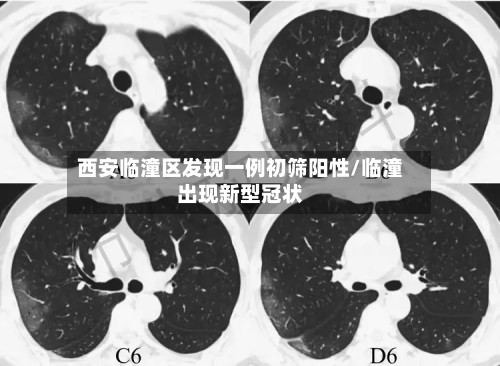

• 西安临潼区发现一例初筛阳性/临潼出现新型冠状

西安有多少粒〖壹〗、例如,2024年4月4日,西安市花粉浓度曾达到4690粒/1000平方毫米,过敏风险等级极高,提示春季树木花粉的致敏风险不容忽视。花粉浓度预测与影响花粉浓度受季节和天气共同影响。秋季天气转凉时,蒿草花粉浓度反而上升;春...